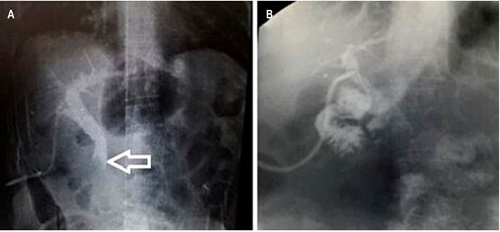

Durante el posoperatorio, el paciente permaneció en la UCI por varios días, con soporte inotrópico y respiratorio. Resuelta la emergencia, y ante la buena evolución, se realizó una colangiografía por el tubo en T (enero 9 de 2019), la cual identificó un defecto de llenado en la porción distal del colédoco, que alcanzó un diámetro de 18 mm, con defecto de llenado, que sugirió la presencia de un cálculo. No se evidenció el paso del medio de contraste hacia las asas intestinales. Se determinó un diagnóstico de síndrome biliar, al parecer, secundario a coledocolitiasis (Figura 2).

Asimismo, por vía endoscópica, se completó la fragmentación y la extracción de los cálculos, mediante el uso de una canastilla de Dormia (Figura 3) y de un balón extractor. Se realizó una colangiografía por el tubo en T y se observó un adecuado paso del medio de contraste al duodeno, sin extravasaciones de este, y sin evidencia de cálculos residuales (Figura 2B).